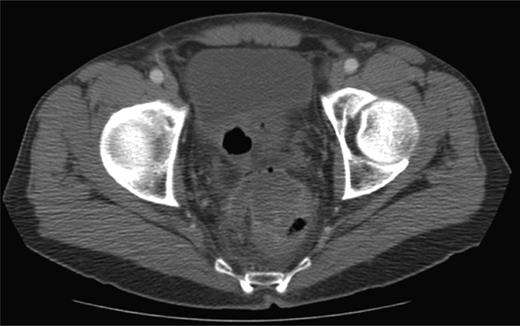

In the 6-week follow-up, repeat CT demonstrated eccentric thickening of the rectosigmoid with interval development of an adjacent complex pelvic fluid collection with supralevator extension measuring 3.5 × 2.5 cm (Fig. 2a and b). Percutaneous needle biopsy revealed pus, and a drainage catheter was left in place (Fig. 3a and b). The patient did not improve, was reimaged and was found to have collection extending into the ischiorectal fossa and supralevator space (Fig. 4). Owing to refractory pain and persistent leukocytosis, the patient was taken to the operating room for examination under anesthesia. No fistulous tract or internal drainage was noted within the rectal vault; however, consistent with the imaging, external induration was observed along the right ischiorectal fossa, where, upon incision, a large purulent cavity was evacuated. On evening rounds, the patient was noted to have a marked leukocytosis and frank stool coming from the ischial wound, and he was taken emergently to the operating room for diagnostic laparotomy where a perforated diverticulum adherent to the pelvic sidewall was identified (Fig. 5). Therefore, a Hartmann procedure, drainage of supralevator abscess, irrigation and debridement of the right ischiorectal wound, was performed.

(a) Repeat CT at 6 weeks showing supralevator abscess formation (white asterisk). The levator ani muscle is illustrated by white arrow (b) coronal image of complex supralevator collection. Arrow points to the levator ani muscle.